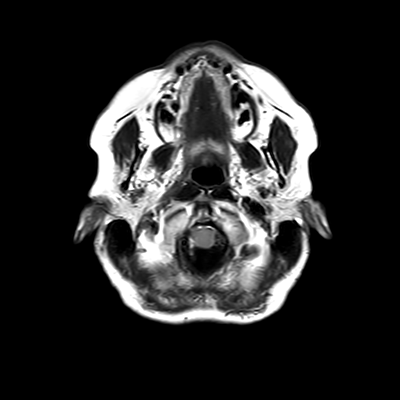

You also obtain an MRI of his brain once it's clinically safe to do so.

MRI brain (FLAIR)